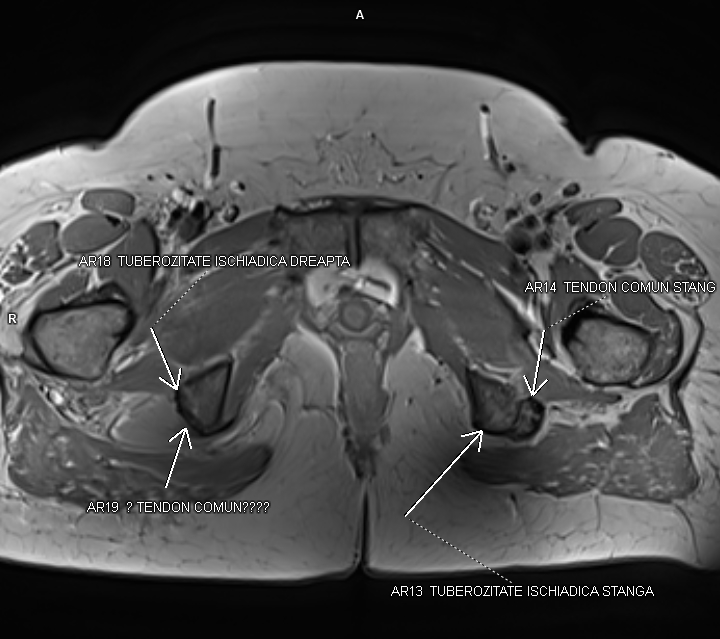

Figurile 5, 6 si 7: axial T1 coapsă bilateral

Discuţie caz nr 92: Harmstring lesion este dificil de tradus în limba română și se referă la leziunea celor trei mușchi ce se inseră pe tuberozitatea ischiadică: semitendinos, semimebranos și biceps femural. Cazul prezentat este a unui pacient care s-a aplecat la cumpărături să ridice o plasa și a simțit o durere puternică în spatele coapsei urmată de impotența funcțională si de creștere de volum a coapsei posterior. Pe imaginile postate se evidențiază avulsia tendonului comun al celor trei muschi ce se regăsește retractat inferior cu formarea unui hematom în vecinătate.